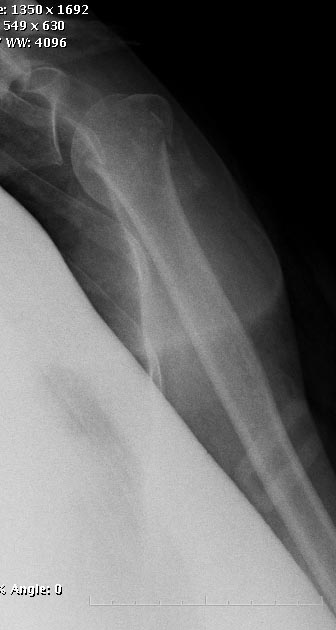

Идеальный случай для закрытого интрамедуллярного остеосинтеза проксимальным плечевым гвоздем. Если есть кто-то знающий, как это правильно сделать. Хороших железок сейчас доступно немало, Synthes Multiloc, Stryker T2 PHN, Versanail PHN... Можно, конечно, и пластиной, но это не так sexy.

Уважаемые коллеги, наш с Вами любимый сайт читают и посещают не только маститые ученые и профессора, но и просто практикующие врачи, ординаторы и студенты. Вопрос: в представленном клиническом случае диагноз "Трехфрагментарный ... и т.д." и предложенные несколько способов РЕМОНТА этого перелома (другого термина я не могу применить в предложениях уважаемых учёных) основаны ТОЛЬКО НА ПРЕДСТАВЛЕННОЙ РЕНТГЕНОГРАММЕ???!!!

А другие проекции рентгенограмм? А КТ? А, общий статус пациентки? А "все эти глупости с кальциями, альфами-D3 и т.д., на которые тратится много времени и денег", - ГДЕ ВРАЧЕВАНИЕ? ГДЕ КЛИНИЧЕСКИЙ ПОДХОД?

> уважаемых учёных) основаны ТОЛЬКО НА ПРЕДСТАВЛЕННОЙ РЕНТГЕНОГРАММЕ???!!!

> А другие проекции рентгенограмм? А КТ? А, общий статус пациентки?

Все остальные проблемы лечащий врач на нас не взваливает. Попросили подсказать по узкому вопросу. Спрашивающий доктор, ограничиваясь этим снимком, задает граничные условия для поиска решений. Подразумевая, что то, что мы видим, исчерпывающе характеризует проблему. То есть, чего на снимке нет - того и нет. Если информации было бы недостаточно для выбора - об этом сразу бы сказали. А так - эта картинка очень типичная, и обсуждение показывает, что в основном участникам ситуация ясна...